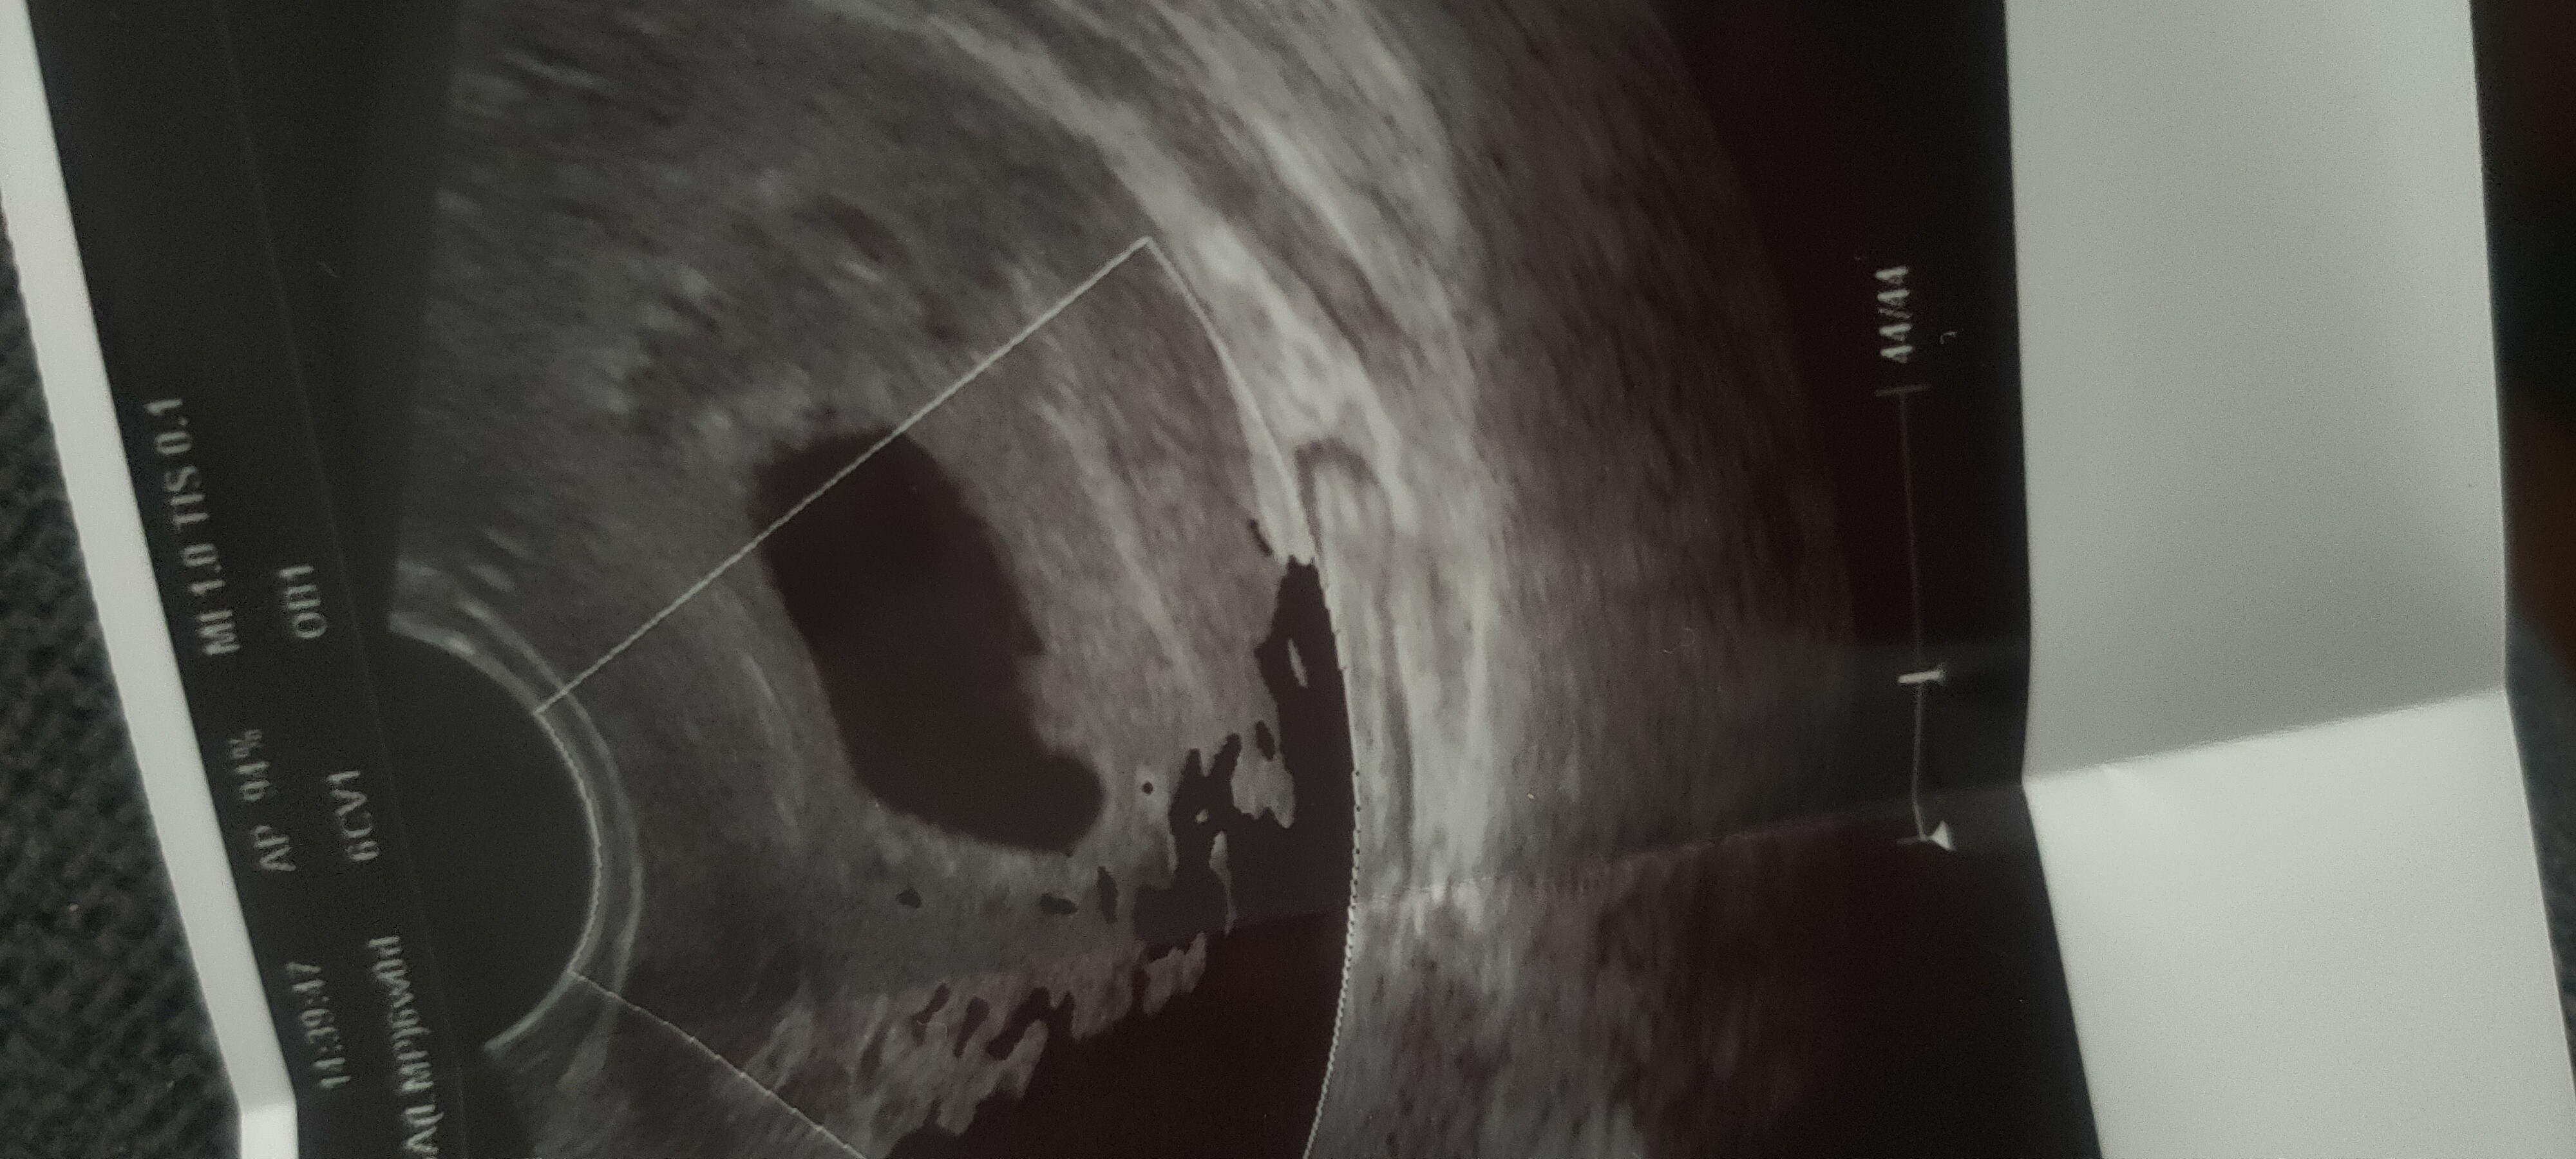

Witajcie, ja też wróciłam właśnie z wizyty dzisiaj 6+1 ,brak zarodka , lekarka kazała zbadać betę i pojawić się za tydzień ... Eh 🥺 jednak miałam dobre przeczucia..

Załączniki

• IMG20210625180048.jpg

IMG20210625180048.jpg

1,5 MB · Wyświetleń: 115